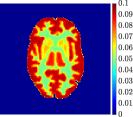

Figure 4, Figure 5, and Figure 6 show the mean images computed over the ten reconstructions obtained by the methods reg-AS-TR, reg-GN, and by the Matlab routine lsqcurvefit implementing a standard Trust-Region-Reflective least-squares algorithm [11, 10]. We used the noise-free IF and the perturbed IF with and of noise, respectively. Figure 7 contains mean and standard deviation values of the kinetic parameters computed over the ten reconstructions and over each one of the four homogeneous regions, for each one of the three noise levels on the IF.

In general, reg-AS-TR and lsqcurvefit seem to provide similar mean reconstructions, although uncertainties associated to lsqcurvefit are significantly bigger. On the other hand reg-GN seems to systematically underestimate the parameter values within region . Furthermore and as expected, for all methods the quality of the parametric reconstructions deteriorates with increasing noise levels; this is more clear from the and parametric images, probably due to the different sensitivities of the data with respect to the model parameters [37]. In reg-GN and lsqcurvefit some artifacts can be observed at the edges of the homogeneous regions, especially around region and region , whereas the effect of regularization in reg-AS-TR results in a reduced presence of artifacts while the structure of the regions is preserved. This general trend is confirmed by the error-bar plots of Figure 7. Finally, the frames in Figure 8 corresponding to reg-AS-TR show a significant improvement of the image quality with respect to what is provided by the other two approaches.